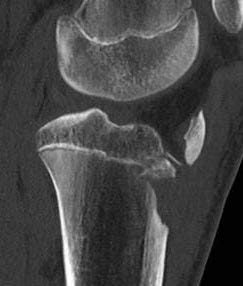

CT / MRI scan

CT scan - ensure fracture doesn't involve the physis / disrupt articular surface

Type IB

Type IIB

Type III

Comminuted Type III